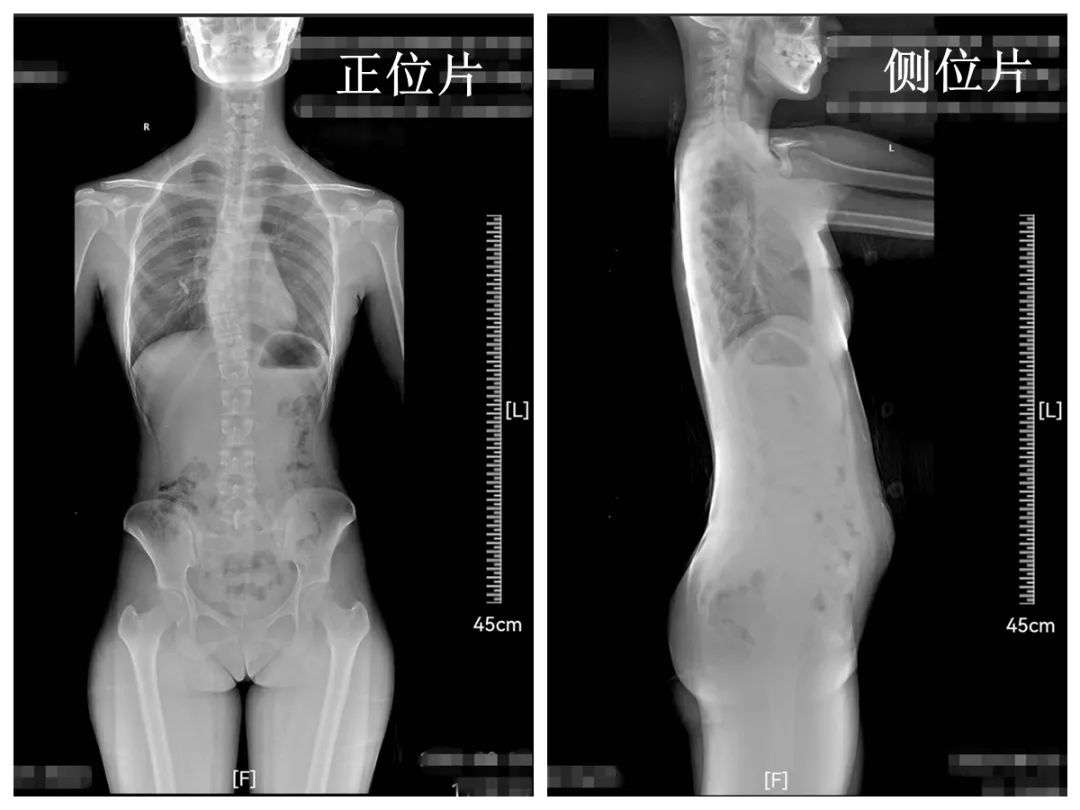

▲脊柱侧弯诊断金标准:

站立位下全脊柱X光线